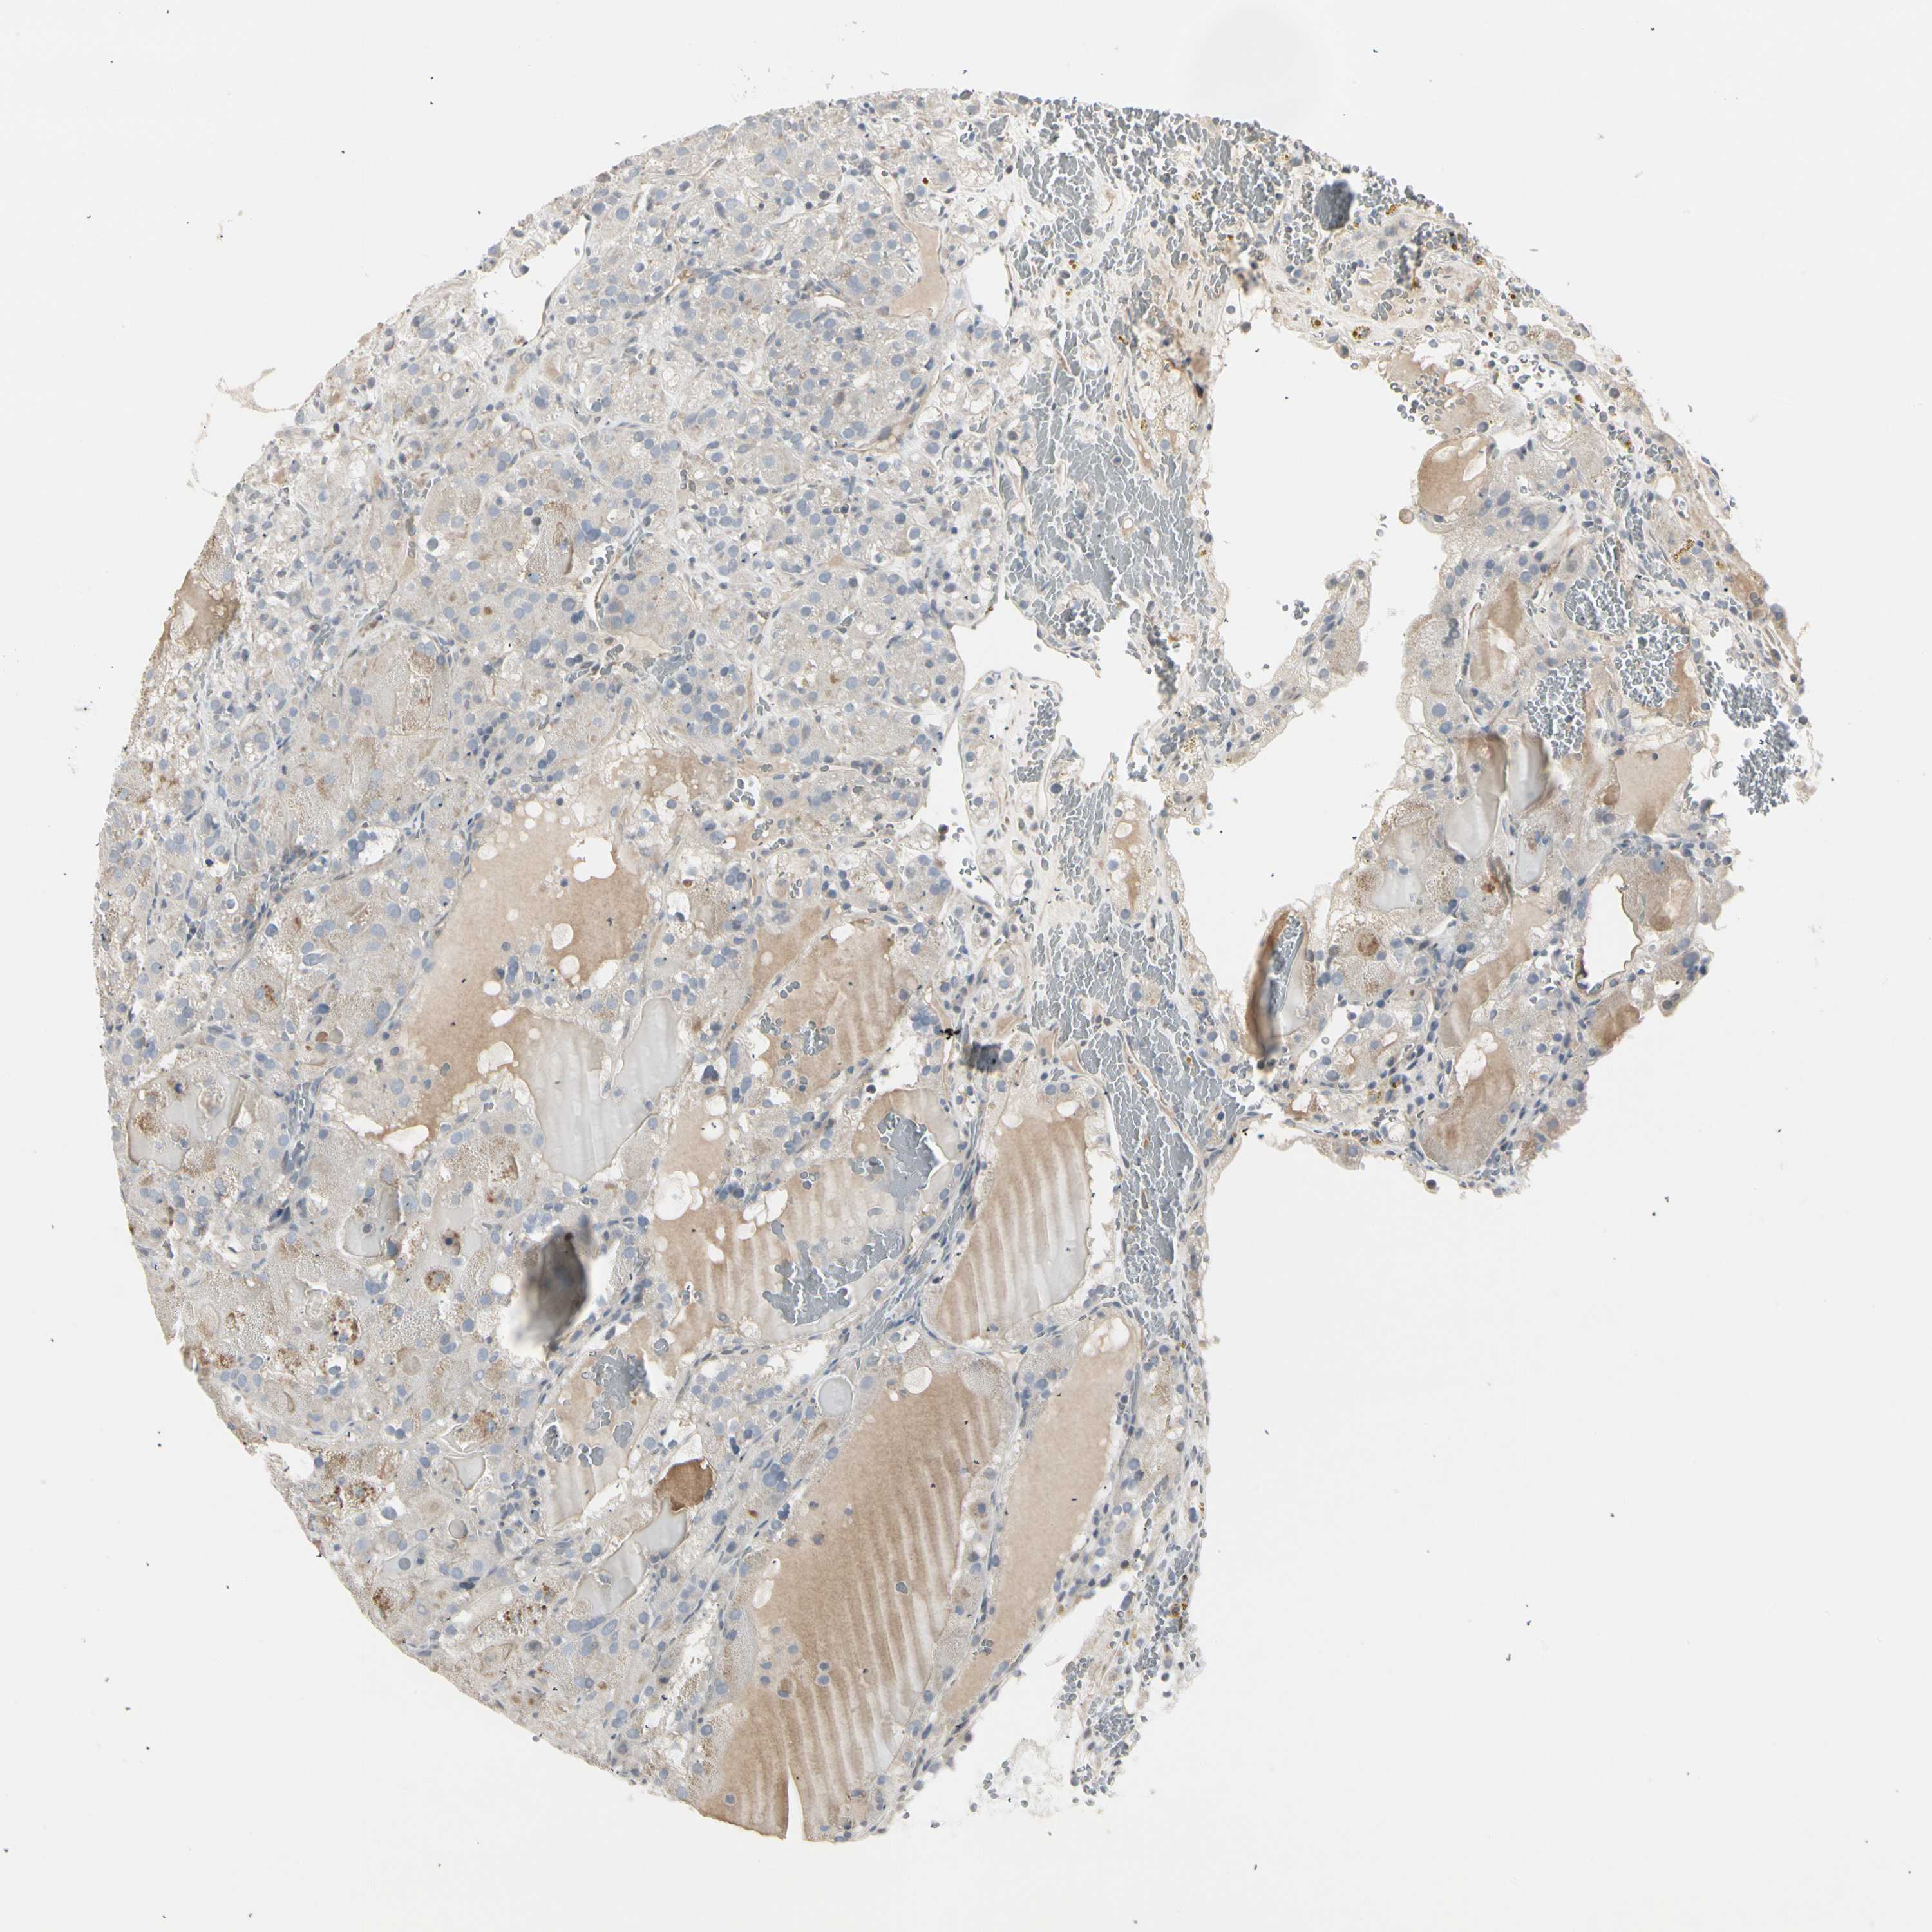

CANCER RENAL CANCER Show tissue menu

KICH TCGA KIRC TCGA KIRC VALIDATION KIRP TCGA PROTEIN RCC CPTAC PROTEIN EXPRESSION